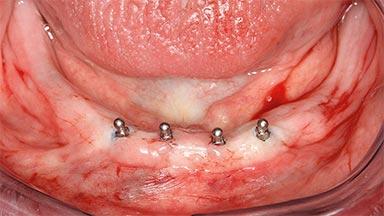

Four Immediately Loaded Mini-Implants Supporting a Mandibular Overdenture

A 74-year-old male patient, a non-smoker, who had been wearing complete dentures for more than 30 years, presented to our clinic complaining about discomfort in connection with his lower denture. The patient suffered from asthma and had a history of cardiac disease and blood pressure disorders. All conditions were medically controlled and stable. The clinical inspection of the oral cavity revealed an ill-fitting complete mandibular denture. The patient expressed the wish for his lower denture to “stop moving when chewing, swallowing, and speaking.” He reported having heard about dental implants and asked whether these could help in “fixing” his lower denture, but also requested non-invasive treatment. The mucosa presented healthy and was free of defects such as pressure sores. An band of keratinized mucosa approximately 2 mm wide was visible. The patient’s mucosal biotype was medium thick to thin.

# of Implants 4

Type of Implants One-Piece|Reduced-Diameter